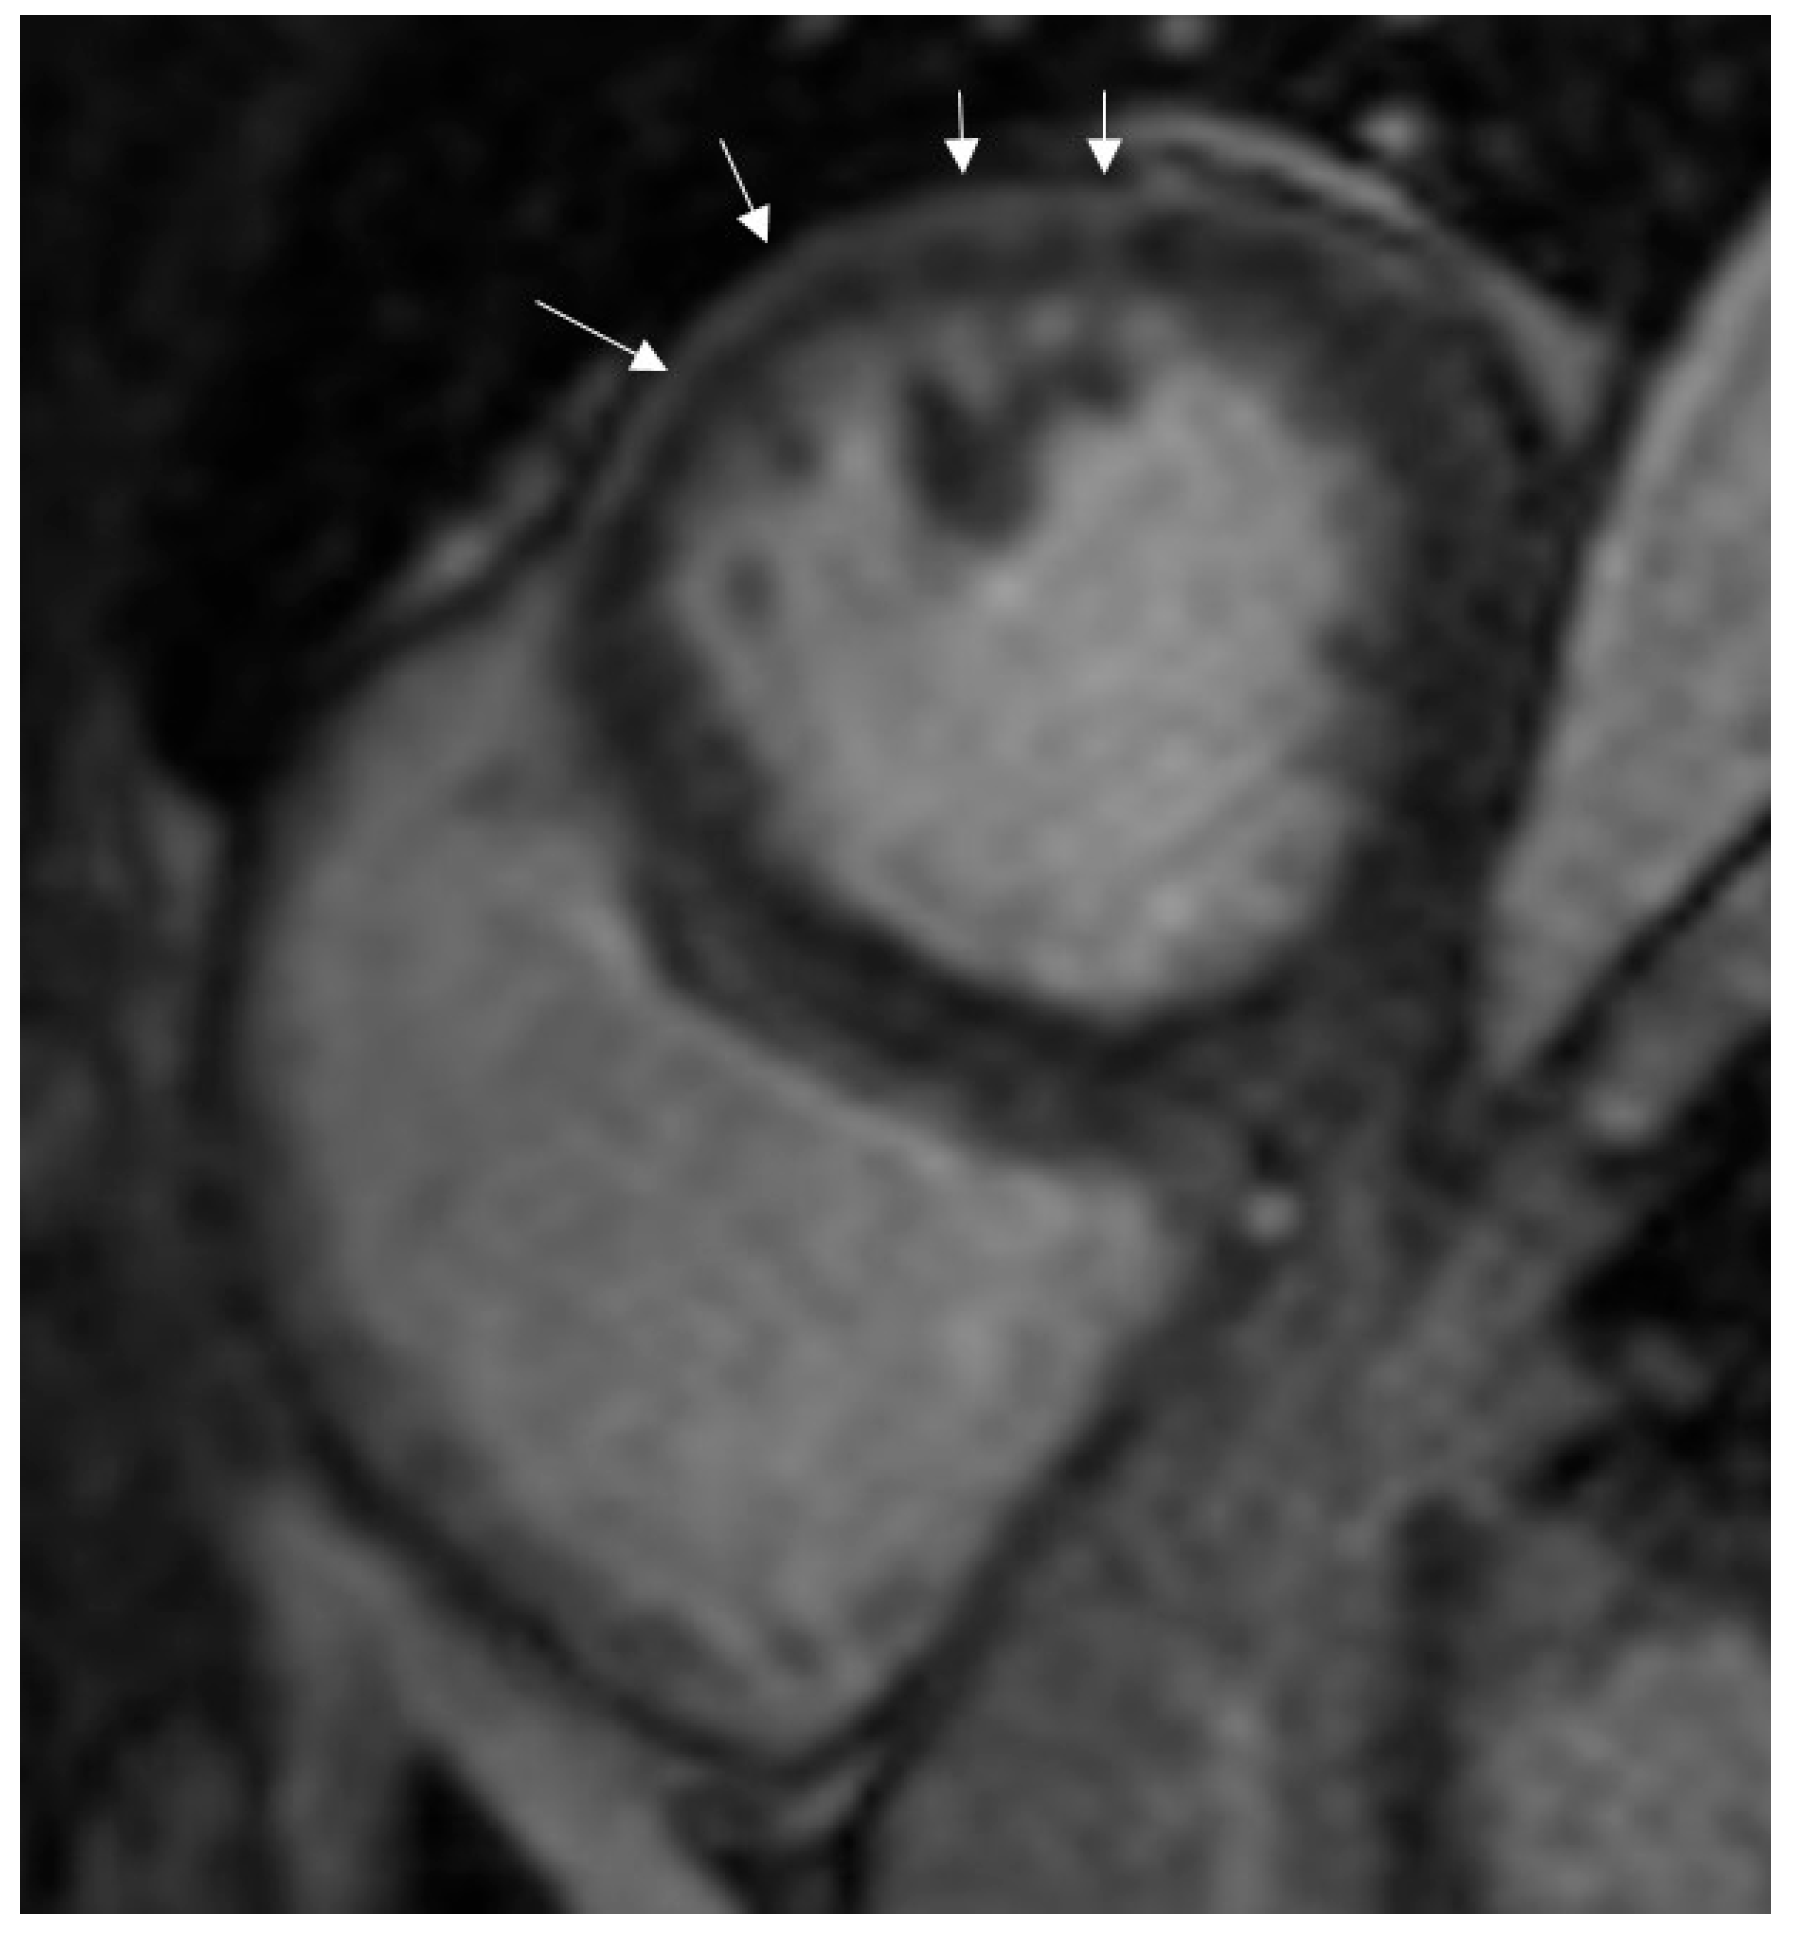

The most common LGE pattern was subepicardial enhancement, observed in 50% of COVID-19 myocarditis patients (Figure 2), followed by mid-wall (8%) and ischemic (4%) patterns.

Figure 2. Subepicardial enhancement in late-gadolinium images (arrows).